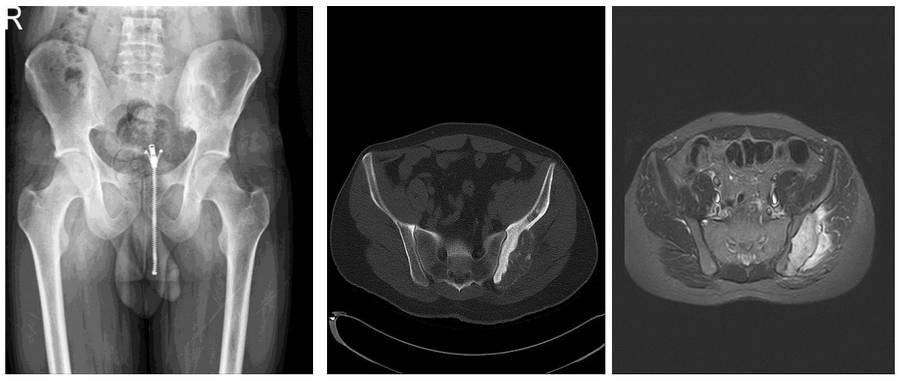

Preoperative examination: X-ray shows irregularity in the posterior aspect of the left iliac wing, CT scan shows bone destruction, and MRI shows an accompanying soft tissue component.